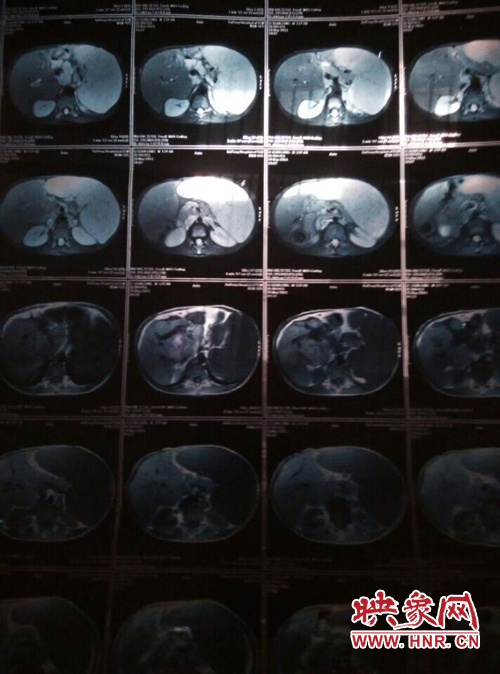

他叫李乾龍,今年16歲,家住寧陵縣城郊鄉(xiāng)李莊村,家里有四口人,目前在寧陵縣黨校就讀上高一,他一邊上學一邊看病,十幾年來,他們跑遍了大小醫(yī)院,卻一直沒查出他的病因。16歲的他發(fā)育的還沒有13歲的弟弟高,肚子大的像個皮球,經常身體發(fā)熱,全身無力,因為沒錢去大醫(yī)院檢查治療只得在家保守治療。